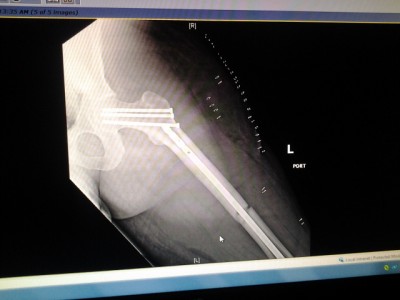

So... To start, I had a motorcycle accident and broke my leg in two places. They had to insert a rod and a bunch of screws in. But I think I had nerve damage. How I know? Well the outside of both my legs to the small toes are numb. Not totally, I have feeling. But they're numb.

I had the accident on 4-7-14. Been non-weight bearing on my left leg since.

Attachment:

2014-04-10 08.08.20.jpg

2014-04-10 08.08.20.jpg [ 84.72 KiB | Viewed 5366 times ]

2014-04-10 08.07.56.jpg

2014-04-10 08.07.56.jpg [ 91.21 KiB | Viewed 5366 times ]

Just don't ask me how my bike fared :/